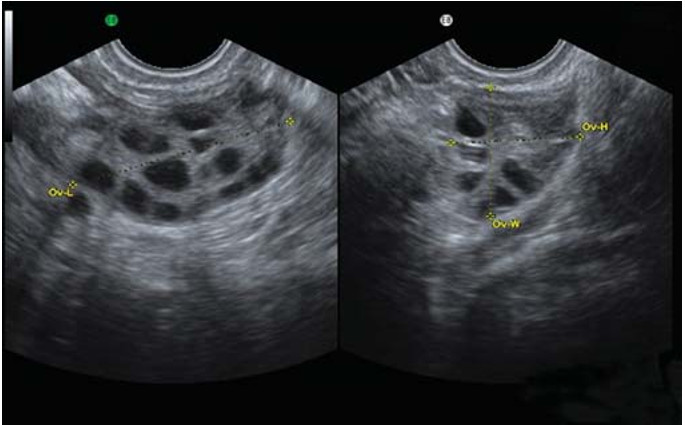

在做超声检查时发现两边卵巢长出许多小囊(内含有卵子),这些小囊大小约2~8mm,小囊数目每边卵巢约10个以上,会导致卵巢发育不正常且无法定期排卵。

影像学检查发现卵巢有变大的情形,或是在卵巢发现超过12颗以上的滤泡。